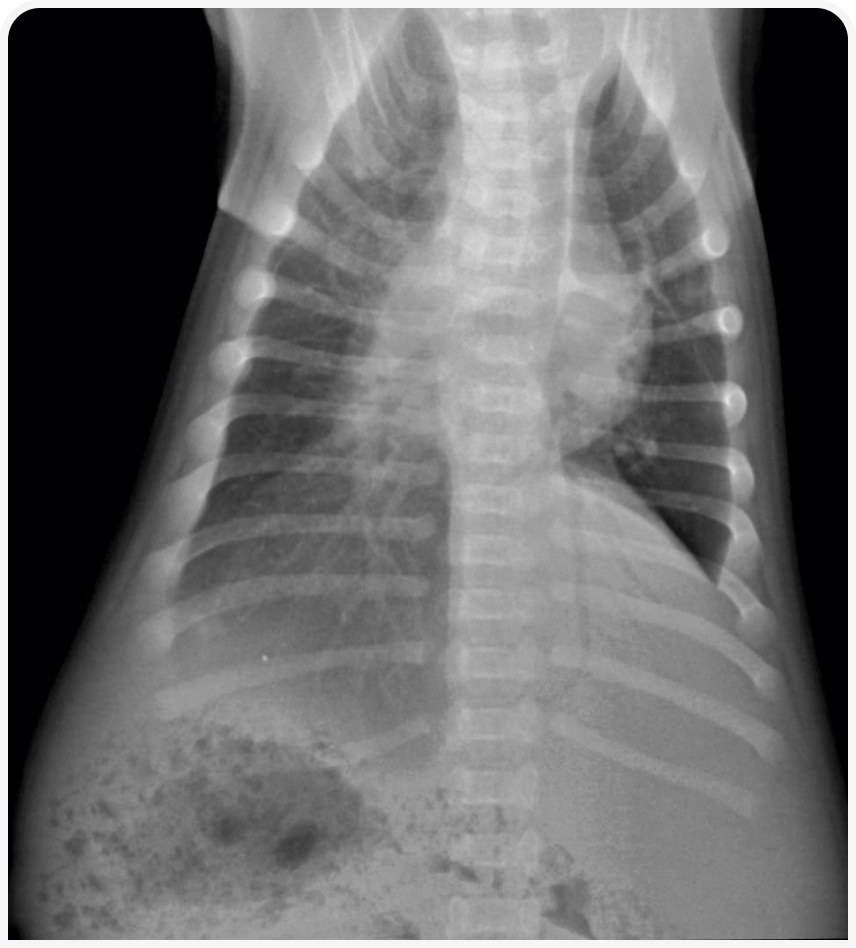

Рентгенографическое и ультразвуковое исследования могут быть не информативны, поскольку многие патологические для взрослых результаты могут не иметь никакого значения у новорожденных (Рисунок 4). Например, у 60% щенков в первые две недели (и у 30% в возрасте одного месяца) наблюдается перитонеальный выпот, не вызывающий клинических последствий; жидкость спонтанно рассасывается. Аналогичным образом, у 40% щенков на 2-й день, у 25% на 7-й день и у 5% в возрасте двух месяцев при УЗИ выявляют расширение почечной лоханки, без каких‑либо клинических проявлений. Кора почек у новорожденных до 14-го дня может иметь два четко выраженных слоя (внешний слой гипоэхогенный, а внутренний более эхогенный). До 21-го дня паренхима селезенки может иметь очень характерную «леопардовую» эхотекстуру, предположительно вследствие активации иммунной системы новорожденного (неопубликованные данные автора).